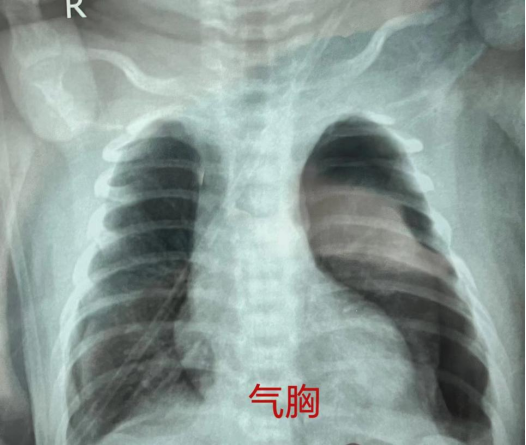

中午12点多,患儿转入新生儿科,许德权副主任带领医护团队,为患儿紧急完善相关检查,确诊为新生儿急性呼吸窘迫综合征并发双侧张力性气胸,遂立即为患儿实施双侧胸腔闭式引流联合高频呼吸机辅助通气。操作顺利完成后,宝宝呼吸困难明显好转,在场的医护人员暂时松了一口气,但他们丝毫不敢懈怠,守护在宝宝身边,时刻关注病情变化。